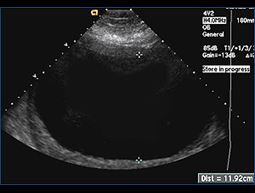

Ultrasound is used to identify the placental cord insertion of each baby (colored points).